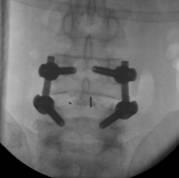

近日,市四医院脊柱创伤外科手术团队在全市较早将微创经椎间孔腰椎椎体融合技术(misTLIF)用于腰椎管狭窄症和腰椎滑脱症患者。手术为经皮微创置钉,在通道下行神经减压椎体复位及椎间融合,手术切口仅有几厘米,手术创伤小,患者术后次日可下床。完成该手术的两名患者腰腿痛症状缓解,手术取得明显成效。

misTLIF手术是近年来发展起来的一项骨科新技术,主要用于腰椎管狭窄症、腰椎滑脱症。它与传统的开放手术相比,有着明显优势,术中切口小,创伤出血少,且无需广泛切开肌肉韧带等软组织,避免了因肌肉软组织剥离过多而导致的迟发性脊柱不稳;由于手术创伤小,术后患者恢复快,可以尽早下床活动,减少了术后切口感染以及卧床时间过长带来的一系列并发症。